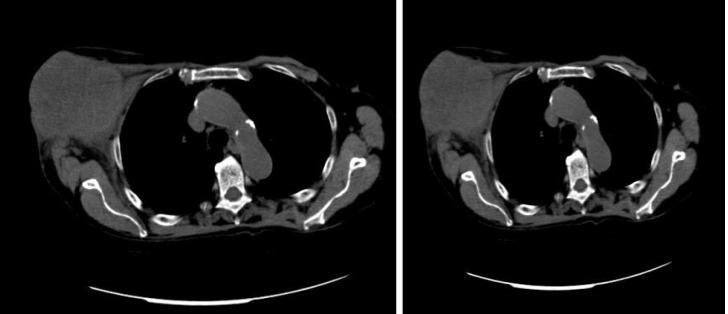

We report a case of synchronous massive breast metastasis from CRC in an 85 year old patient who came to the hospital presenting a huge mass originating from the axillary extension of the right breast. A whole body computed tomography also showed a mass in the right colon. The patient underwent a simple right mastectomy along with right hemicolectomy. The resected breast showed massive metastasis from CRC with intense and homogeneous nuclear CDX2 staining, while the colon specimen revealed poorly differentiated adenocarcinoma stage pT4a pN0 pM1 (breast) (Tumor Node Metastasis 2017). Three months later she developed a subcutaneous mass at the site of the previous mastectomy. An ultrasound guided biopsy was carried out again and revealed a metastasis from CRC. The patient then started treatment with capecitabine plus bevacizumab, obtaining stable disease (RECIST criteria) and a clinical benefit after 3 mo of therapy.

我们报告一例85岁患者发生同步性CRC乳腺巨大转移的病例,该患者因右乳腋窝延伸处出现巨大肿块前来就诊。全身计算机断层扫描还显示右结肠有一个肿块。患者接受了单纯右乳房切除术及右半结肠切除术。切除的乳腺显示有CRC的大量转移,核CDX2染色强烈且均匀,而结肠标本显示为低分化腺癌,分期为pT4a pN0 pM1(乳腺)(2017年肿瘤淋巴结转移分期)。三个月后,她在先前乳房切除部位出现皮下肿块。再次进行超声引导下活检,结果显示为CRC转移。然后患者开始接受卡培他滨加贝伐单抗治疗,治疗3个月后病情稳定(根据实体瘤疗效评价标准)并获得临床获益。